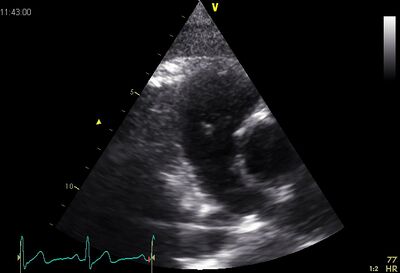

Echocardiographic views

Pulm art02.jpg Pulm art03.jpg

PSAX ao Plax by tilted